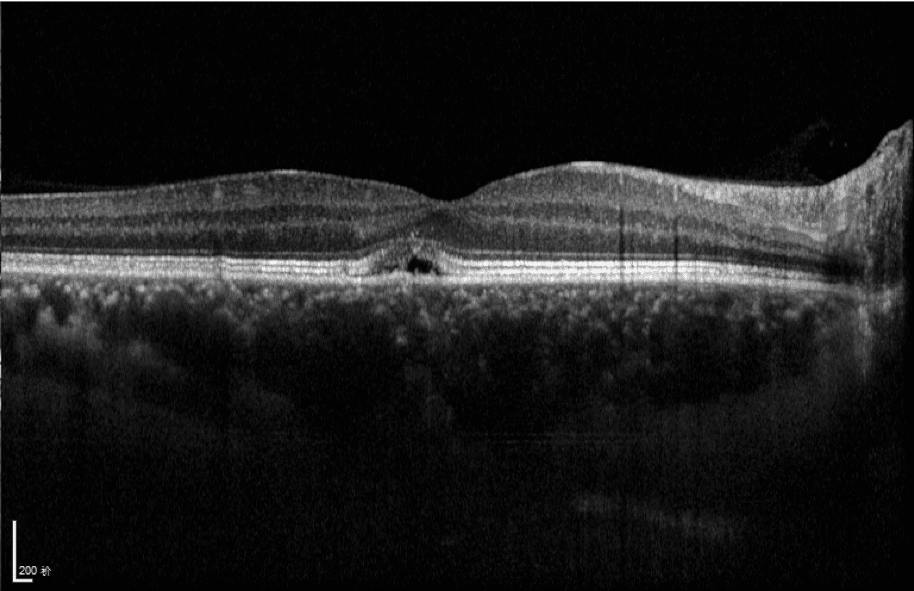

- Choroid OCTA with Quantification Parameters